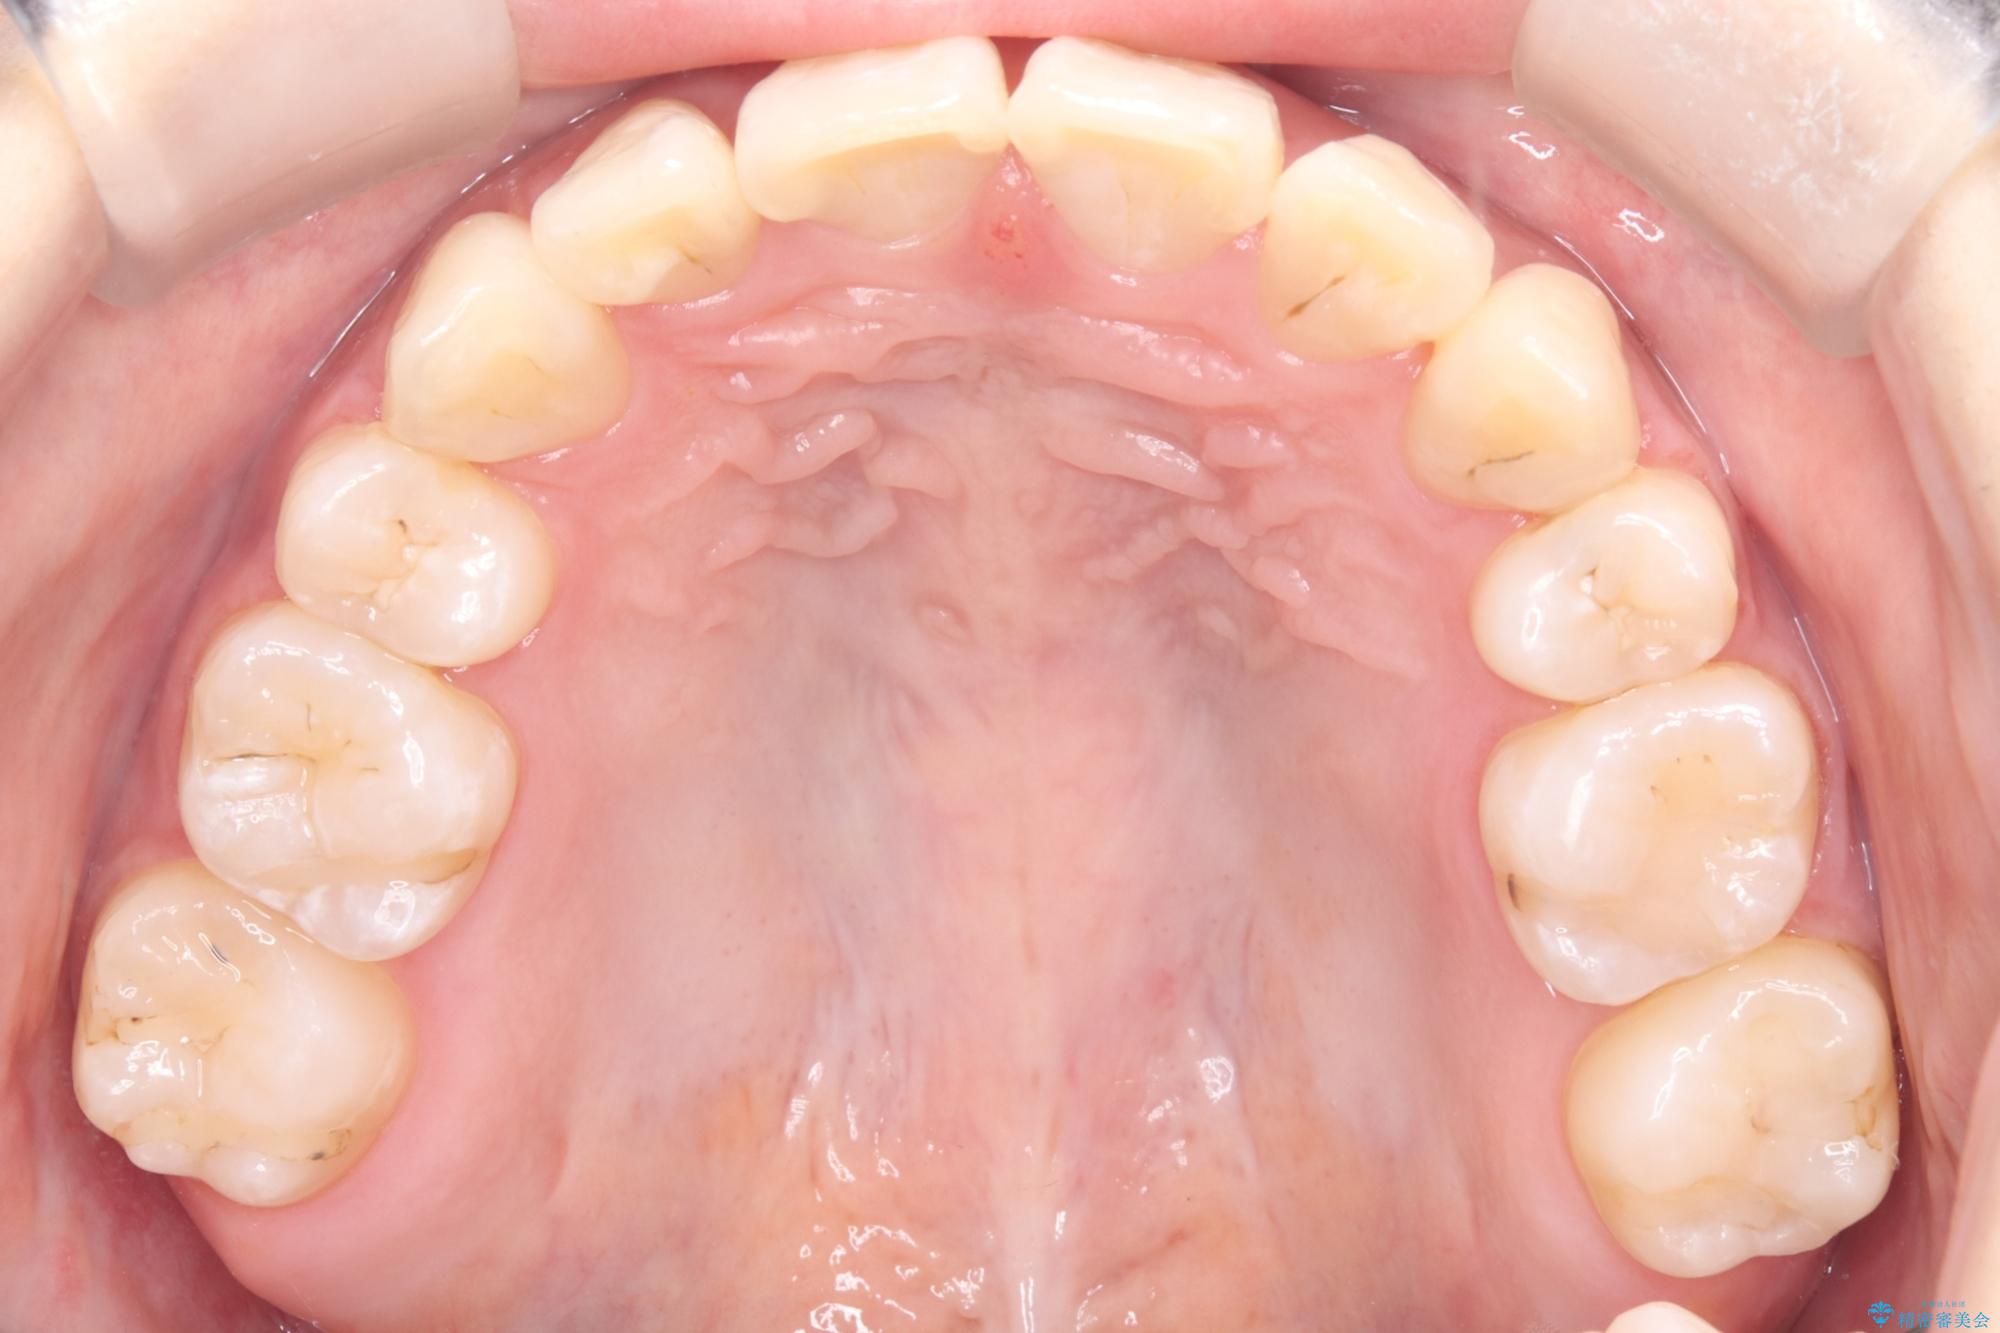

今回の矯正治療では、まず計画通り上下左右の小臼歯4本を抜歯し、八重歯や正中のズレを解消するための十分なスペースを確保しました。装置には、目立ちにくい白いブラケットとワイヤーを使用した審美ワイヤー矯正を採用。

八重歯: 突出していた八重歯を歯列内に誘導し、デコボコを解消しました。

正中のズレ: 歯を左右対称に移動させることで、上下の歯の中心線を正確に合わせ、顔全体のバランスも改善しました。

治療の結果、長年気にされていた八重歯と正中のズレが解消し、機能的にも整った理想的な歯並びを獲得。目立たない装置で治療を完遂し、自信を持って笑える美しい笑顔を手に入れていただけました。